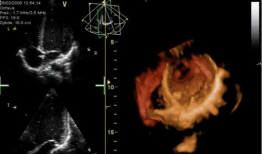

心脏跳动的视频,揭秘心脏跳动的奥秘

你知道吗?最近在网上流传着一个特别神奇的视频,它记录了心脏跳动的瞬间。这可不是普通的视频,它让我们仿佛能感受到心跳的力量,那种感...